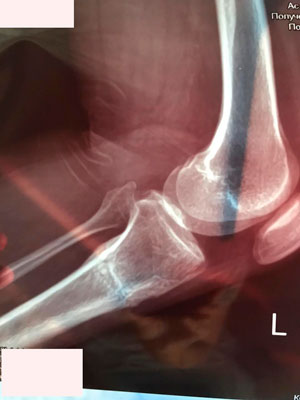

Дата операции - 15.06.2019г.

Дата снятия аппаратов - 25.09.2019г.

Срок сращения - 100 дней.